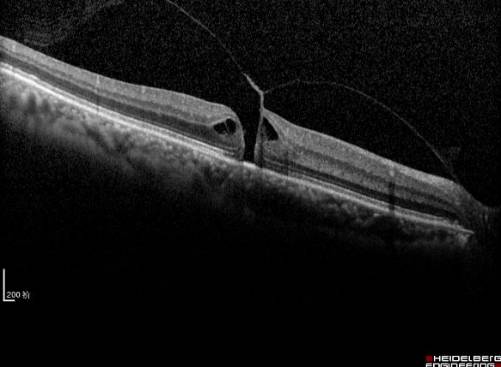

黄斑裂孔

随着年龄的增加,玻璃体浓缩、凝聚,玻璃体后界面与视网膜表面发生不同程度的后脱离。在脱离的过程中,由于在黄斑区域两者结合十分紧密,局部玻璃体黄斑牵拉,导致粘连的视网膜组织被撕脱下来,就形成了黄斑裂孔。因年龄造成的黄斑裂孔常无明确可循的原因,称为特发性黄斑裂孔。其他常见的原因还有外伤或高度近视等。黄斑裂孔一旦形成,会严重影响视力,应及时采取玻璃体手术封闭裂孔,可以有效阻止视力的进一步降落,术后视力提高的病例临床也不少见(见图8和图9)。

玻璃体手术采用局部麻醉、术中无痛感。具体手术方法主要行玻璃体切除术后,切除黄斑区粘连的玻璃体,解除玻璃体黄斑牵拉,同时撕除裂孔周围的视网膜内界膜,封闭裂孔。术中有可能在玻璃体腔内填充气体,通过气泡的顶压作用促进裂孔愈合。极少数特殊患者,需要填充硅油。如果患者合并白内障,联合超声乳化白内障手术,植入合适的人工晶体,术后视力更令人满意(见图8和图9)。

目前黄斑手术进入了微创时代,手术创伤更小、效果更确定、患者几乎无痛苦。通过手术治疗,裂孔封闭率达到90%以上。当然,手术成功率与术后视力恢复情况主要取决于病程长短、裂孔大小、牵拉的程度范围,尤其是术者的手术技巧。黄斑手术联合白内障手术,术后有的患者视力可达到0.8以上。